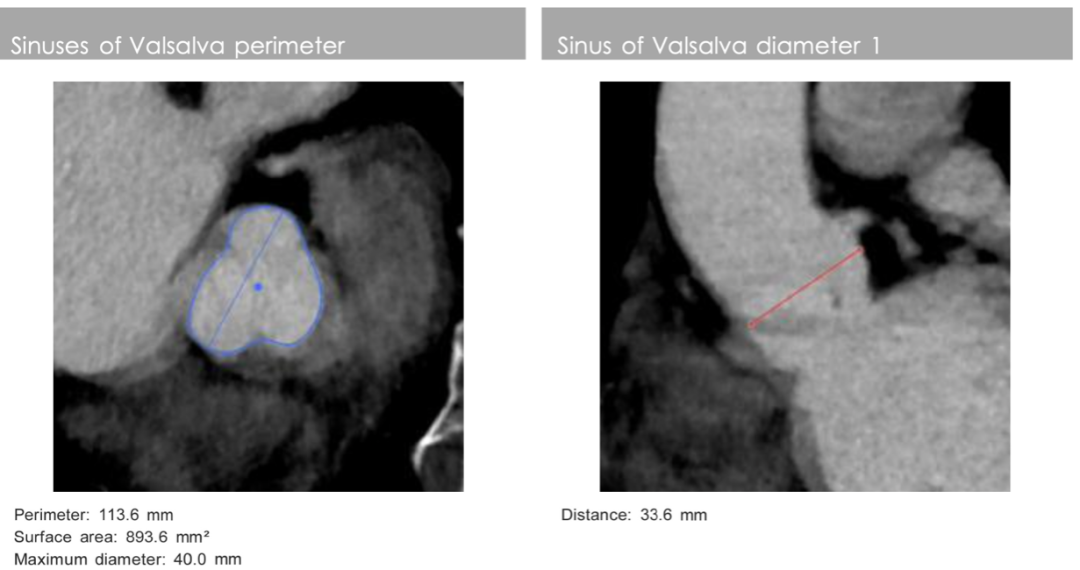

影像分析